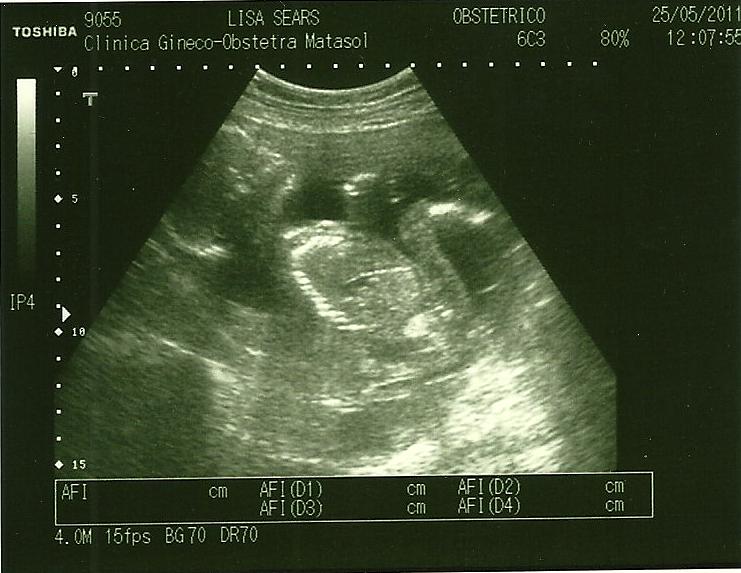

And now the one from today, without any zooming in. In fact, it was out as far as possible!

Note the length of the legs and torso...definitely my little Giant! And now for indisputable proof of gender, a picture that will be used later for blackmail...=)

Yeah, that's not the umbilical cord. The doc assured us of the fact that it is a boy. In fact, she said, "Look at the little turtle." I about died laughing!